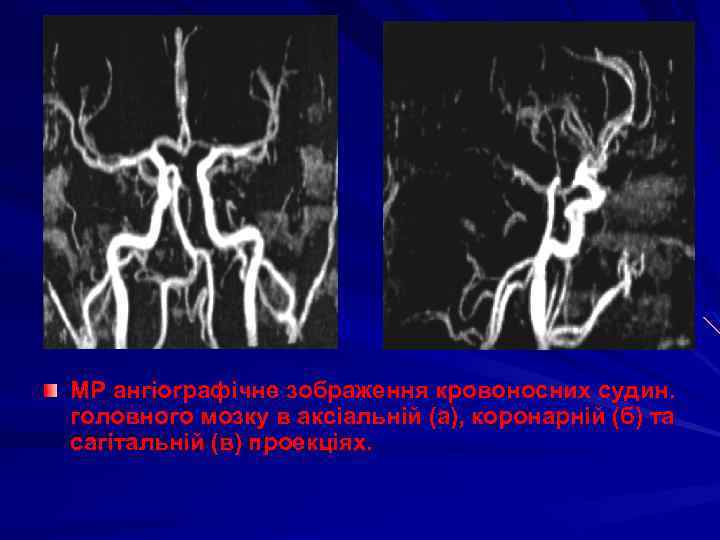

МР ангіографічне зображення кровоносних судин. головного мозку в аксіальній (а), коронарній (б) та сагітальній (в) проекціях.